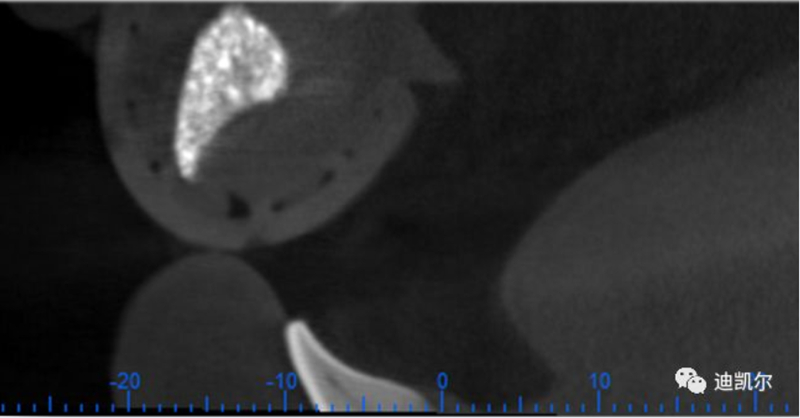

*CBCT顯示骨缺損嚴重,種植窩洞制備困難,種植體很難獲得初期穩(wěn)定性

患者佩戴此U型管開合拍攝CBCT,U型管中的放射標記點清晰顯影